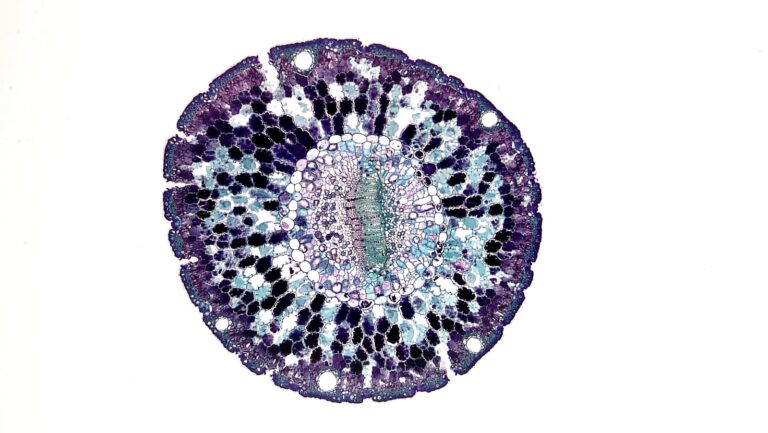

● Durchflusszytometrie: Die Durchflusszytometrie ist ein wertvolles Instrument zur Beurteilung der Funktion des Immunsystems, indem sie die Verteilung und Funktion von Immunzellen, insbesondere T-Zellen und B-Zellen, analysiert. Sie hilft bei der Diagnose von Erkrankungen wie schwerer kombinierter Immundefizienz (SCID).